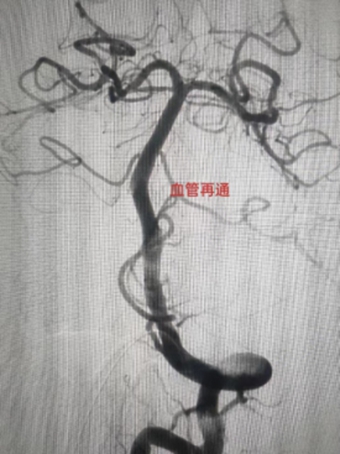

1、左侧颈内动脉末端闭塞,急诊导管抽栓+支架拉栓1例;